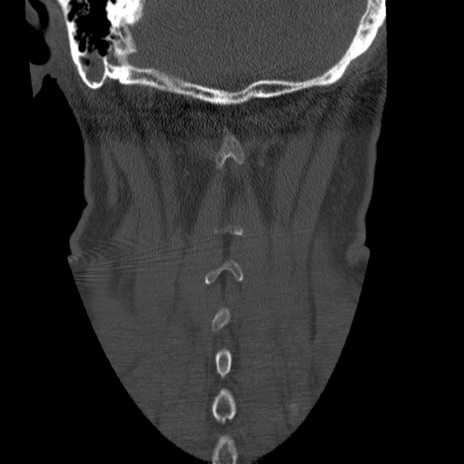

症例50 頚椎CT(冠状断像)

【症例】60歳代女性

【主訴】後頭部〜右後頸部にかけての痛み

【現病歴】本日飲食店でコーヒーを飲んでいたところ、突然後頭部〜右後頸部にかけて痛みが出現し、右上肢の感覚障害を伴ったため救急要請。

【身体所見】脳神経学的に明らかな異常所見を認めず。右上肢に軽度の感覚障害あり。

異常所見と診断は?

頚椎CT